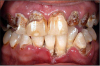

Dental Caries: Meth mouth, or crank decay, is commonly observed in methamphetamine users. The cause of meth mouth is multifactorial. Meth users commonly experience drug-induced cravings for high-calorie carbonated beverages. As a result, soft drinks containing high amounts of sugar and caffeine are often consumed to prolong the high and assuage the cravings. Reports indicate that Mountain Dew is commonly ingested by meth users; as much as several liters per day. The drug produces extreme xerostomia, reducing the amount of protective saliva and buffering capacity around the teeth. As a result of these behaviors, the oral bacterial levels can drastically increase, exacerbating the decay. The caustic nature of the drug, poor oral care and high sugar diet result in increased decay. This devastation can occur rapidly in as little as one year. Conventional dental treatment is frequently of little value. Often, the caries are so significant and rampant that full-mouth extractions are indicated (Figure 13).

Periodontal Disease: Methamphetamine users have an increased incidence of periodontal disease. The drug causes vasoconstriction of the vessels that supply blood to the oral tissues. With repeated use of the drug and repeated vasoconstriction, the blood vessels are permanently damaged and the oral tissues die. In addition, lack of proper daily oral hygiene further exacerbates the declining periodontal health.

Bruxism: Methamphetamine can cause users to feel anxious and nervous, resulting in clenching and grinding of the teeth. Signs of bruxism, including fractures of the teeth and severe attrition, are common. The vasoconstriction can also affect the vitality of the teeth, increasing the likelihood of enamel fractures.